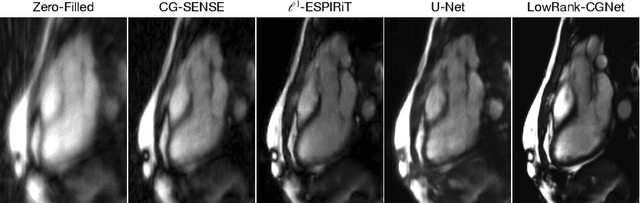

Cardiovascular diseases (CVDs) remain the leading cause of mortality and morbidity worldwide. Both diagnosis and prognosis of these diseases benefit from high-quality imaging, which cardiac magnetic resonance imaging provides. CMR imaging requires lengthy acquisition times and multiple breath-holds for a complete exam, which can lead to patient discomfort and frequently results in image artifacts. In this work, we present a Low-rank tensor U-Net method (LowRank-CGNet) that rapidly reconstructs highly undersampled data with a variety of anatomy, contrast, and undersampling artifacts. The model uses conjugate gradient data consistency to solve for the spatial and temporal bases and employs a U-Net to further regularize the basis vectors. Currently, model performance is superior to a standard U-Net, but inferior to conventional compressed sensing methods. In the future, we aim to further improve model performance by increasing the U-Net size, extending the training duration, and dynamically updating the tensor rank for different anatomies.